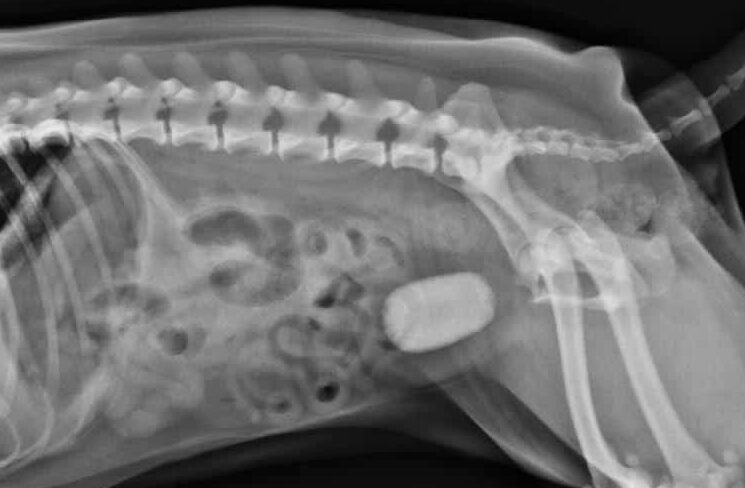

- Radiografía: Algunos cálculos (como las de estruvita y oxalato cálcico) pueden verse en una radiografía abdominal.

Extracción del calculo de la paciente carlina de la previa radiografía.